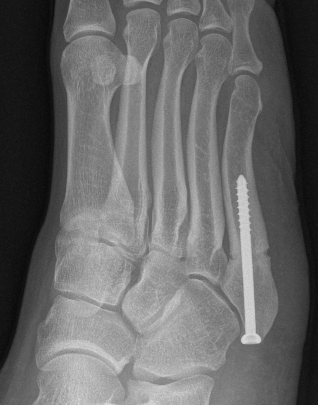

Displaced fracture Nonunion

Intramedullary Screw

Screw fixation Zone 2 nonunion